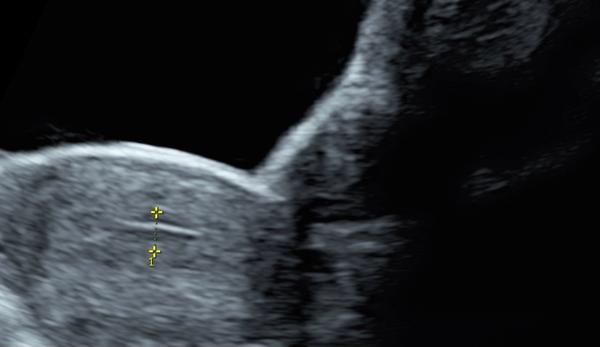

Co znamená čárka na ultrazvuku? Prosím o radu

Víte prosím někdo co to je ta čárka? Díky

Jedná se o ultrazvuk dělohy, břicha to černé je močový měchýř zřejmě